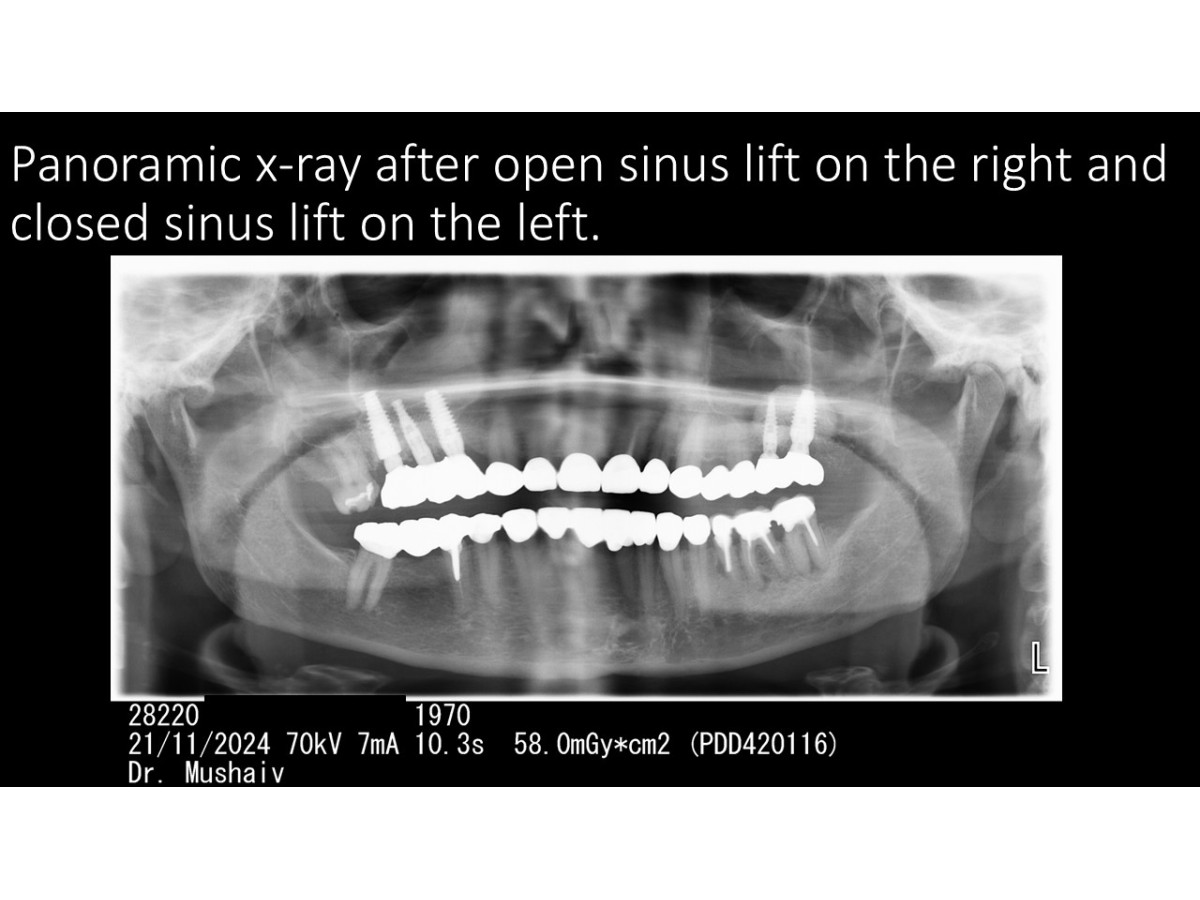

Clinical case: Sinus lifting with immediate implantation, bone augmentation, soft tissue monitoring

Dentist: DDS PhD Ilia Mushayev/Sidhedent, DMi (Israel)